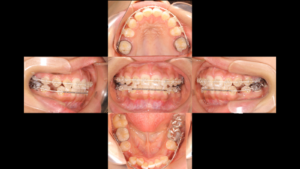

ここで、状態の悪い7番を残して小臼歯だけを抜くのではなく、「リスクの高い7番を抜いて、控えていた8番(親知らず)をその位置へ持ってくる」という戦略を立てました。

診断:安易な抜歯ではなく「リスク」を優先する

通常の矯正では、真ん中あたりの「小臼歯」を4本抜いてスペースを作ることが一般的です。今回の患者様も上下で小臼歯を抜歯しましたが、上顎についてはもう一つの重要な決断をしました。

それは、奥から2番目の歯(7番:第二大臼歯)の状態が非常に悪かった(失活歯)ことです。

ここで状態の悪い歯を残したまま小臼歯だけを抜いて並べても、数年後にその奥歯がダメになってしまったら、また患者様は苦労することになります。そこで、リスクのある7番を抜き、一番奥に控えていた親知らず(8番)を矯正の力でスライドさせて持ってくるという計画を立てました。

下にこれまでの経過を載せていきます。